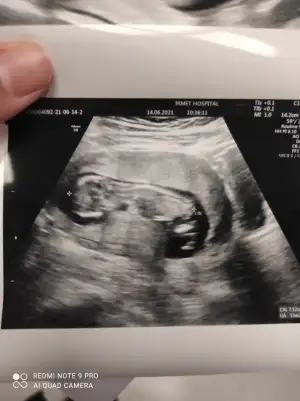

Merhaba erkek demiştin doktor bugün tahmin yaptı erkege benziyor dedi ☺️iki hafta sonra net söyler herhalde değişmezse doğru bildiniz buda 12+3 görüntülerimiz

• IMG_20210614_104639.webp

IMG_20210614_104639.webp

27,6 KB · Görüntüleme: 27

• IMG_20210614_104635.webp

IMG_20210614_104635.webp

32,7 KB · Görüntüleme: 27

• IMG_20210614_104628.webp

IMG_20210614_104628.webp

35,4 KB · Görüntüleme: 26